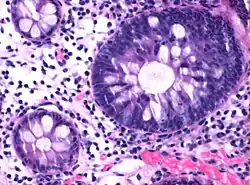

Micrograph of hyperplastic polyp

Histopathologically, there are two main types of hyperplastic polyps, which have genetic differences, as well as different histologic structure, but no significant differences clinically.[4] The two main types of hyperplastic polyps are microvesicular mucin-rich type and goblet cell-rich type.[1] A mucin-poor type with eosinophilic cytoplasm, which is rare, was previously described.[4] However, the mucin poor type is no longer considered a distinct subtype.[1]

Mucin-rich type

The luminal portion has a serrated ("saw tooth") appearance formed by tufts or folds of abundant apical cytoplasm. It contains glands with star-shaped lumina.[4] There are crypts that are elongated but straight, narrow and hyperchromatic at the base. All crypts reach to the muscularis mucosae.[4] The basement membrane is frequently thickened.[4]

Goblet cell-rich type

Elongated, fat crypts and little to no serration. Therefore, they may not be obvious without comparing to adjacent normal intestinal wall.[4]

They are filled with goblet cells, extending to surface, which commonly has a tufted appearance.[4]